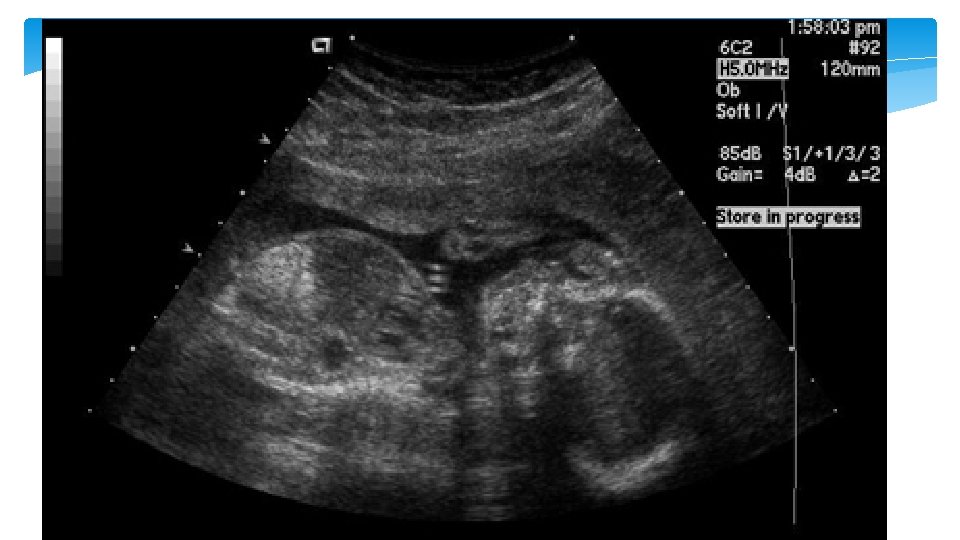

Single umibical artery Is the most common anomaly of the cord and occurs in approximately 1% of all deliveries. It may result from primary aplasia of one of the two umbilical arteries or as a consequence of atrophy of one artery. It is more commen in the left artery and occurs more often in twin gestation. It is sometimes accompanied with abnormal cord insertion in the placenta, i. e. marginal and velamentous cord insertions

Single umbilical artery single umbilical artery (SUA) and an increased risk of aneuploidy when additional fetal malformations are detected. The rate of aneuploidy with isolated SUA is not known, but most experts do not recommend routine chromosomal analysis if there are no other malformations or other indications for genetic amniocentesis.